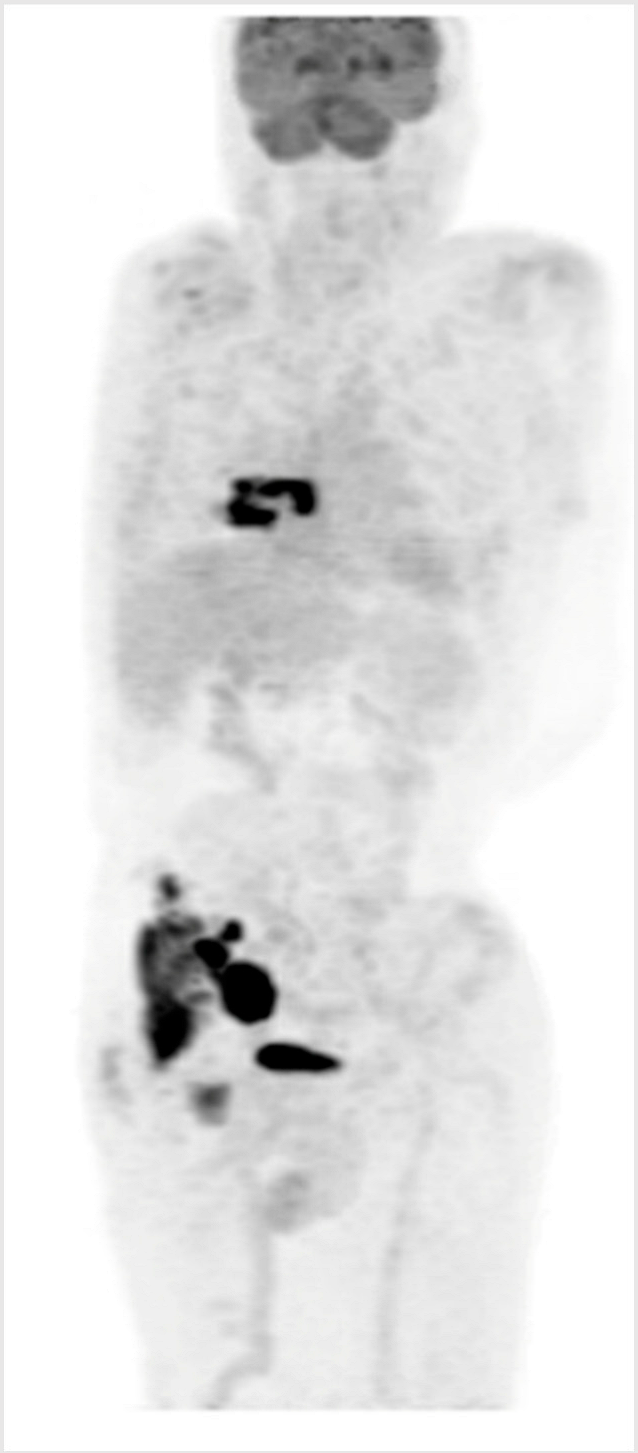

3.4. Illustrative Case 4

Key clinical features

| ![]() |

Key Points for Illustrative Case 4

- Unfortunately, this otherwise healthy man exhibits chemo-refractory disease after an initial benefit from R-CHOP and did not sustain a durable benefit from CAR-T cell therapy;

- BsAbs have demonstrated efficacy for patients with R/R DLBCL regardless of prior exposure to CAR-T cell therapy [1,3]. This case illustrates the potential use of BsAbs following CAR-T cell therapy failure, with CAR-T cell therapy initially prioritized due to its longer available follow-up and known curative potential.